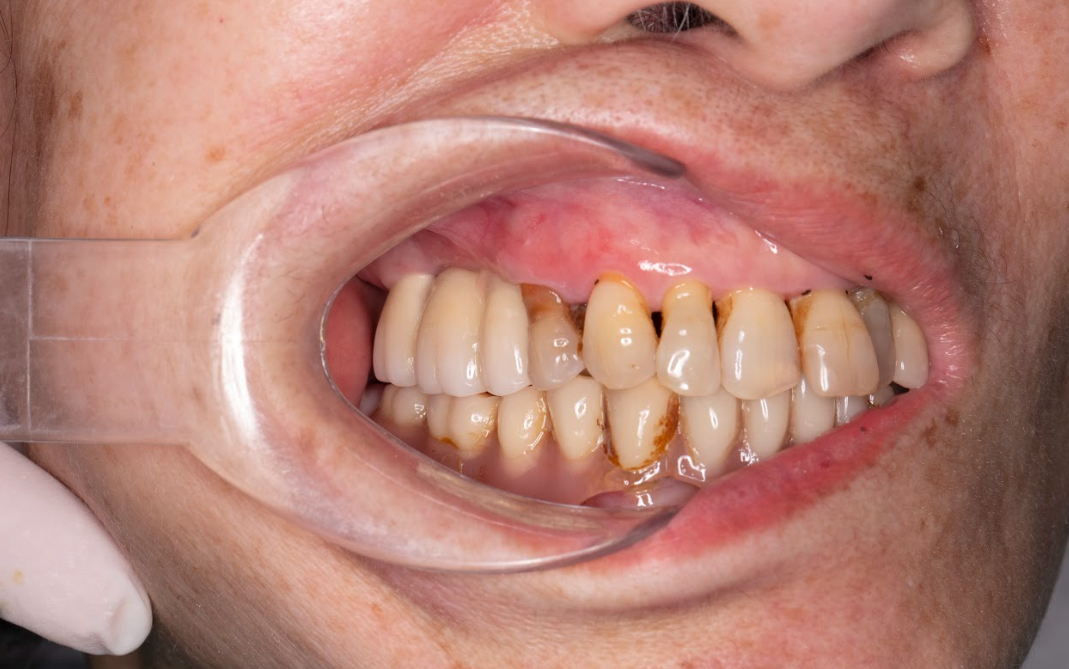

Tình trạng của cô Cúc trước khi trồng răng Implant

Mất nhiều răng cả hai hàm.

Tiêu xương nặng do mất răng lâu năm.

Hàm giả tháo lắp lỏng lẻo, gây đau nướu, không ăn được thức ăn cứng.

Sụt cân nghiêm trọng, chỉ còn 39kg.

Phải truyền chất dinh dưỡng định kỳ để duy trì thể trạng.

Tâm lý chán nản, mất tự tin trong sinh hoạt hàng ngày.